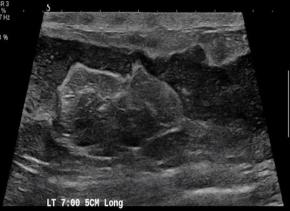

[Breast] 35 /F, Palpable mass, left with redness

Diagnosis Idiopathic granulomatous mastitis

Comments Idiopathic granulomatous mastitis (IGM) is a rare benign inflammatory breast entity characterized by lobulocentric granulomas. IGM has a persistent or recurrent disease course and affects parous premenopausal women with a history of lactation. It has also been associated with hyperprolactinemia. The most common clinical sign is a palpable tender mass. However, the nonspecific manifestations and varied demographic features of this condition, as well as the other similar-appearing and superimposed breast entities, pose substantial diagnostic challenges. Entities with similar manifestations include inflammatory breast cancer (IBC), infective mastitis, foreign body injection granulomas, mammary duct ectasia, diabetic fibrous mastopathy, and systemic granulomatous processes. The strategy for imaging IGM depends on patient age, clinical manifestations, and risk factors. Targeted ultrasonography, mammography, and less commonly, magnetic resonance imaging have proven to be useful for imaging evaluation. Core-needle biopsy, with or without fine-needle aspiration for cytopathologic examination, and culture analysis are usually required to exclude IBC and other benign inflammatory breast processes. Patients with IGM have an excellent prognosis when they are appropriately treated with oral steroids or second-line immunosuppressive and prolactin-lowering medications. However, surgical excision may be an option for patients in whom medication therapy is unsuccessful. Imaging surveillance can be offered to patients with incidentally encountered IGM or mild symptoms. Clinical suspicion for this rare disease and the breast imager’s prompt diagnosis can lead to an improved patient outcome. The purpose of this article is to review the imaging manifestations of IGM in a multimodality case-based format and to describe relevant clinical and imaging-based differential diagnoses. The associated pitfalls, epidemiologic and histopathologic factors, clinical manifestations, natural course, and management of IGM also are discussed.